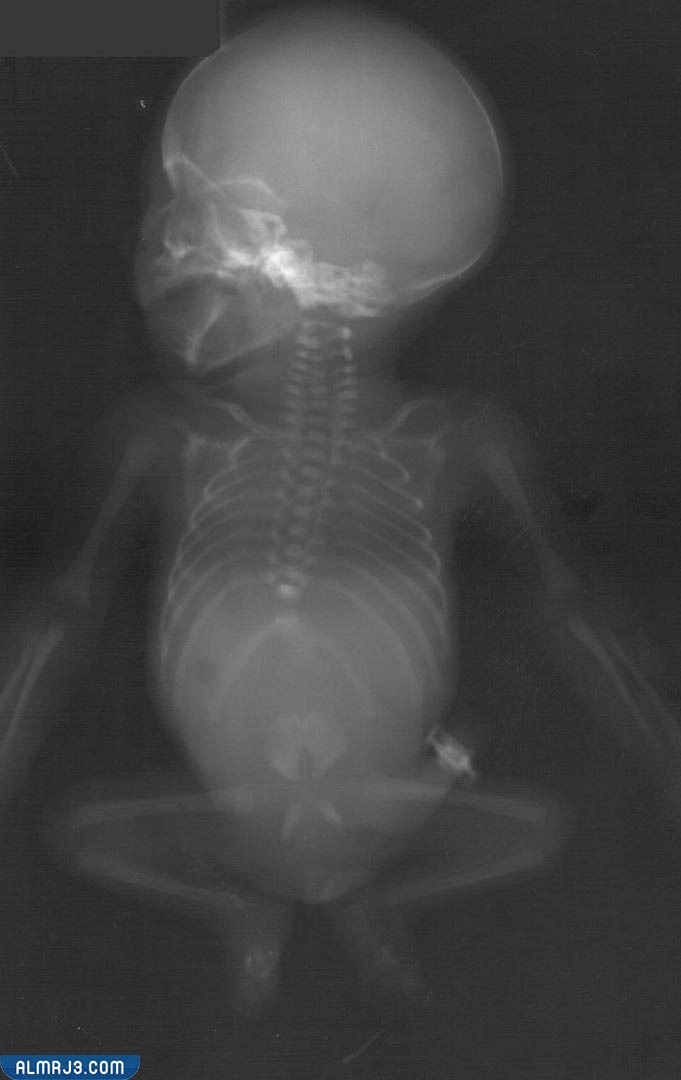

إنّ متلازمة الانحدار أو التراجع الذيلي عيب خلقي اسمه العلمي نقص في نسيج العجز، يصيب الجزء السفلي من العمود الفقري وما يتضمنه من حبل شوكي مما قد يؤثر على الحركة للمصاب، وهو مرض نادر الحدوث معدّل الإصابة فيه 1 مقابل 60 ألف شخص سليم، ومدى الإصابة، وقد يتسبب بتشوهات في العمود الفقري وانحناءات؛ مما يؤثر بحجم وشكل القفص الصدري، وما ينجم عنه من مشكلات في التنفس، لكن التأثير متفاوت بحسب مدى الضرر.[1]

- غياب جزئي وواضح في عظام ذيل العمود الفقري.

- ضمور في الفقرات السفلية والحوض.

- تشوه في شكل وحجم القفص الصدري.

- أطراف سفلية مكفوفة أو ملتصقة.